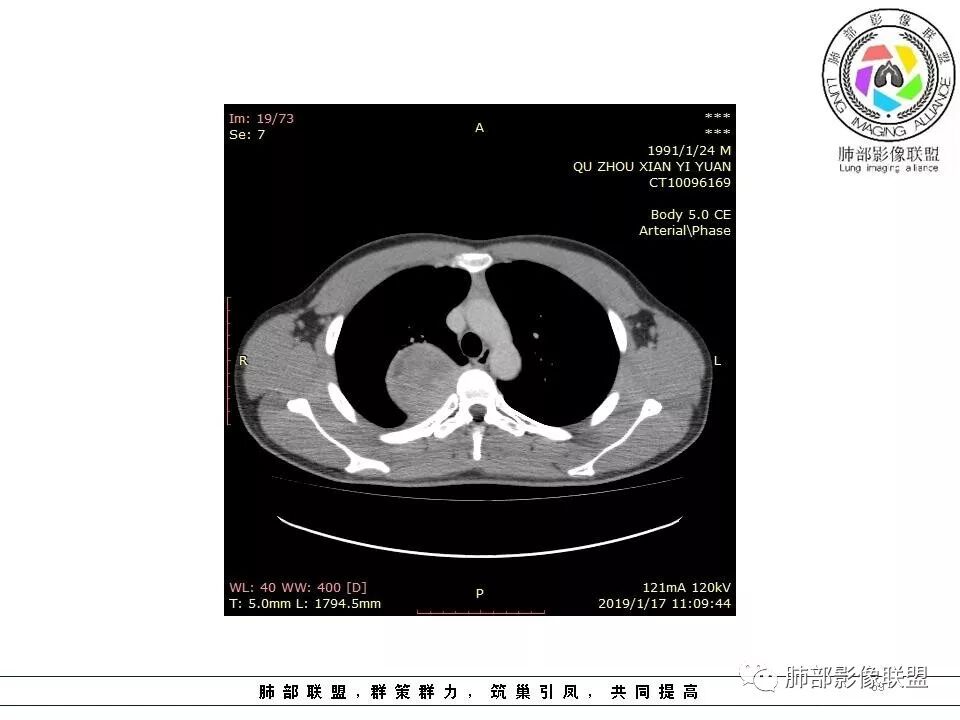

右肺占位,跨越上叶后段、下叶背,边缘光滑,瘤肺界面清,见肺压缩缘(线样不张`强化),见胸膜尾征,胸膜下脂肪未见明显增厚,肋骨丶脊柱未见侵袭及受压,渐进性丶地图样强化,冠状位似见体循环供血

诊断:SFT(来源壁层胸膜?一般小于20%)

鉴别:神经源性(鞘瘤)、LCD、肉瘤丶孤立性间皮瘤

右后纵膈肿块,肺瘤界面清楚,胸膜尾征,邻近肺组织及支气管被推移,部分脂肪间隙存在,定位肺外来源,血供来自肋间动脉,增强后持续渐进强化,蛇纹征,考虑SFT,鞘瘤肿块内血管罕见,不考虑。

青年男性,右侧脊柱旁占位,瘤肺界限清晰,支气管推移,胸膜尾,D字征,胸膜下脂肪影,蛇纹血管,双重供血,延迟强化,定位胸膜,支持sft

病灶边缘清爽,内见蛇形血管影有特征   D字形与胸膜紧贴

轻度强化,未见坏死   支气管向外推挤

边缘光滑,宽基底与胸壁相连,跨叶裂,叶裂稍前推,血管、支气管前移。

浅分叶

外上侧少量胸水

肋间动脉供血,强化尚均匀,逐步强化